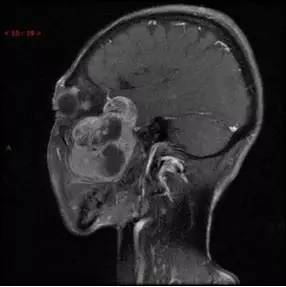

MRI增强冠状位

MRI增强矢状位

解析:本病例为中颅窝至颞下窝沟通性病变,对周围骨质主要呈膨胀压迫性改变,伴囊变、出血。

病理:(中颅底内外沟通肿瘤) 神经鞘瘤,伴出血,局灶细胞较丰富。免疫组化结果显示:EMA(-), P53(-), S100(3 ), NF(-), PR(-), desmin(-), Ki-67( ,5-10%)

神经鞘瘤